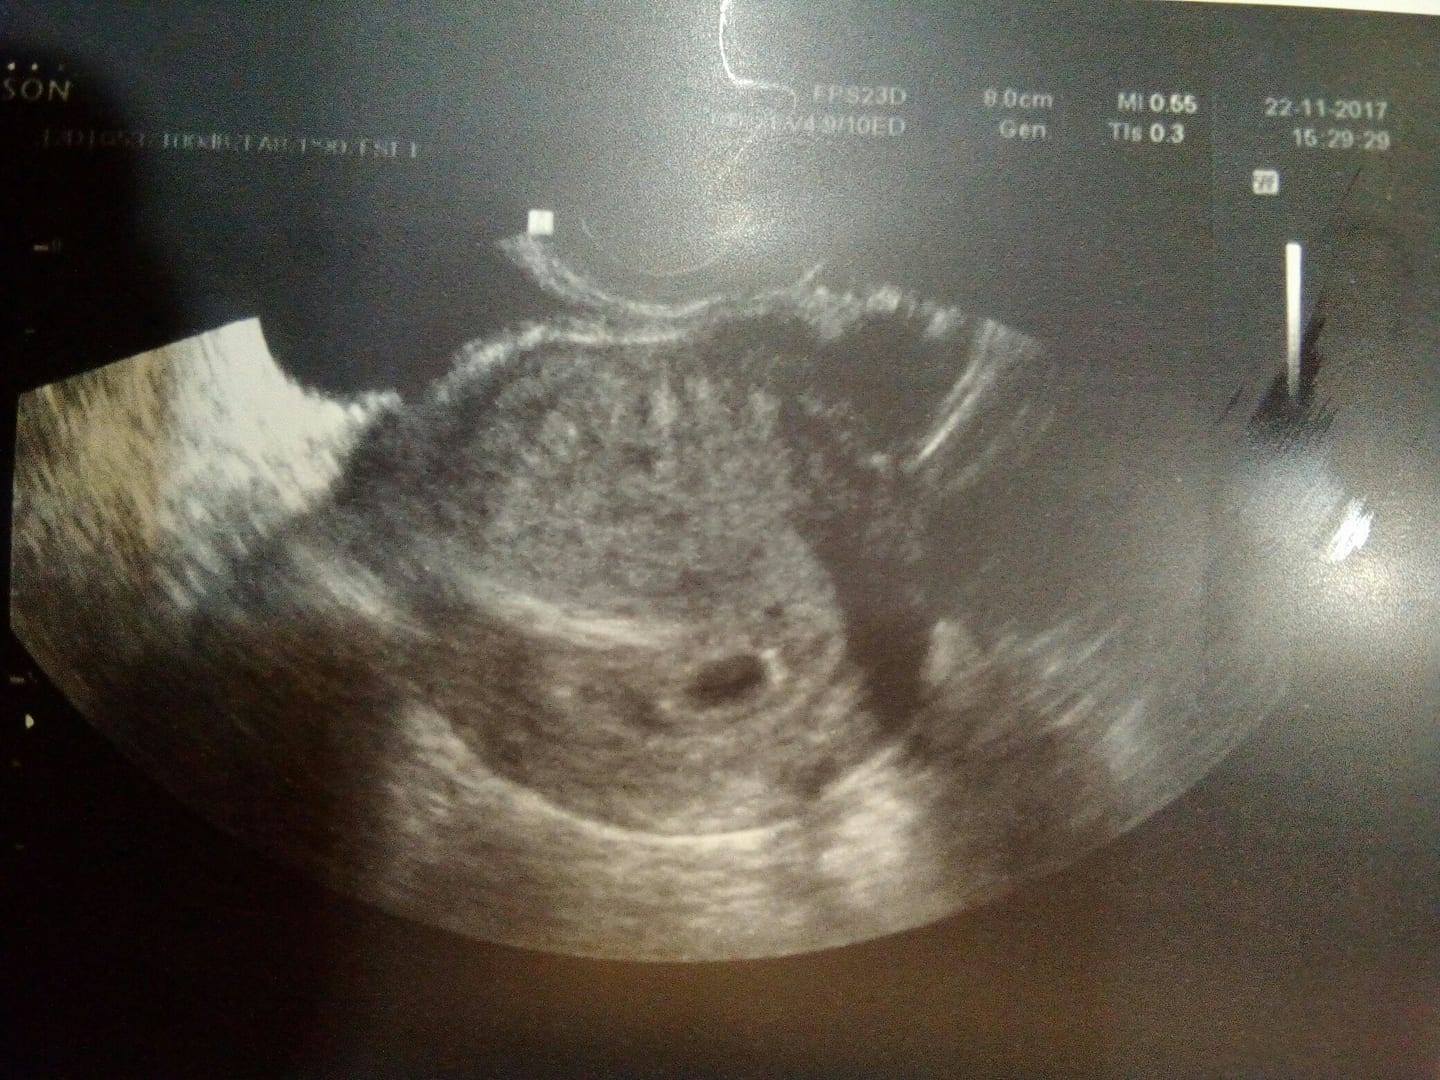

Čekáme miminko, resp.miminka 2. Na uz v 5+4tt byla vidět u A pouze dutinka a B doktor nevěnoval pozornost, ale maličká dutinečka tam byla vidět.

Další UZ jsem byla v 7+2tt a A byla dutinka s prospívajícím embryem odpov.týdnu a nad ním B, které dle dr zaniká.

Ale jak může zanikat, když za těch 12 dní tak vyrostlo? Četla jsem, že je i možné, aby dvojčata od sebe byla třeba delší čas, ale do hlavy my pořád nejde to, že zaniká, když vyrostlo.

Přidávám též obě fotky a moc děkuji za cokoliv, kdo mi napíše